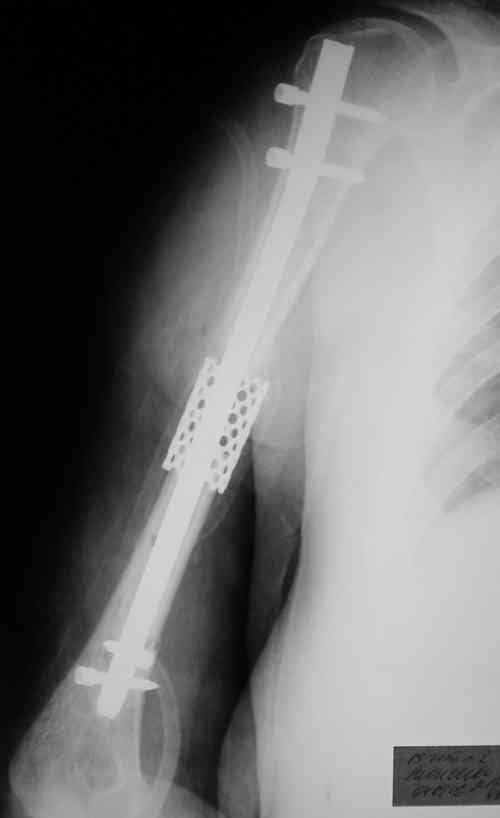

На 3-й день после травмы переведена с делирием в ПСО другой больницы в гипсовой лонгете. Через неделю возвращена, но уже в отделение гнойной хирургии с вторично открытым инфицированным переломом диафиза плеча и флегмоной. Еще через 3 недели хирурги, переведя острый гнойный процесс в хронический вялотекущий, позвали травматолога с целью "сделайте что-нибудь с переломом". Сделали: резекцию остеомиелитичекого очага (перелома, плавающего в гною) около 7 см; стержневой аппарат; цементный спейсор в дефект кости (укоротили плечо на 3 см. и 4 см осталась дырка), бусы из того же цемента с антибиотиком в мягкие ткани. Снимки приложены.

Через 2 недели интрамедуллярный остеосинтез с замещением дефекта кости цилиндрическим металлокаркасом (А.Ф. Лазарев подарил). Дренажи удалили, раны зажили, свищи закрылись. В конце августа благополучно выписана с движениями в локтевом суставе в объеме 0-10-100 град. в плечевом - отведение 45, сгибание -60 (стакан поднять могла).

27.11 в состоянии не прекращающегося после выписки опьянения получила закрытый надмыщелковый перелом плеча на уровне дистальных блокирующих винтов в результате адекватной травмы. Снимки прилагаются.